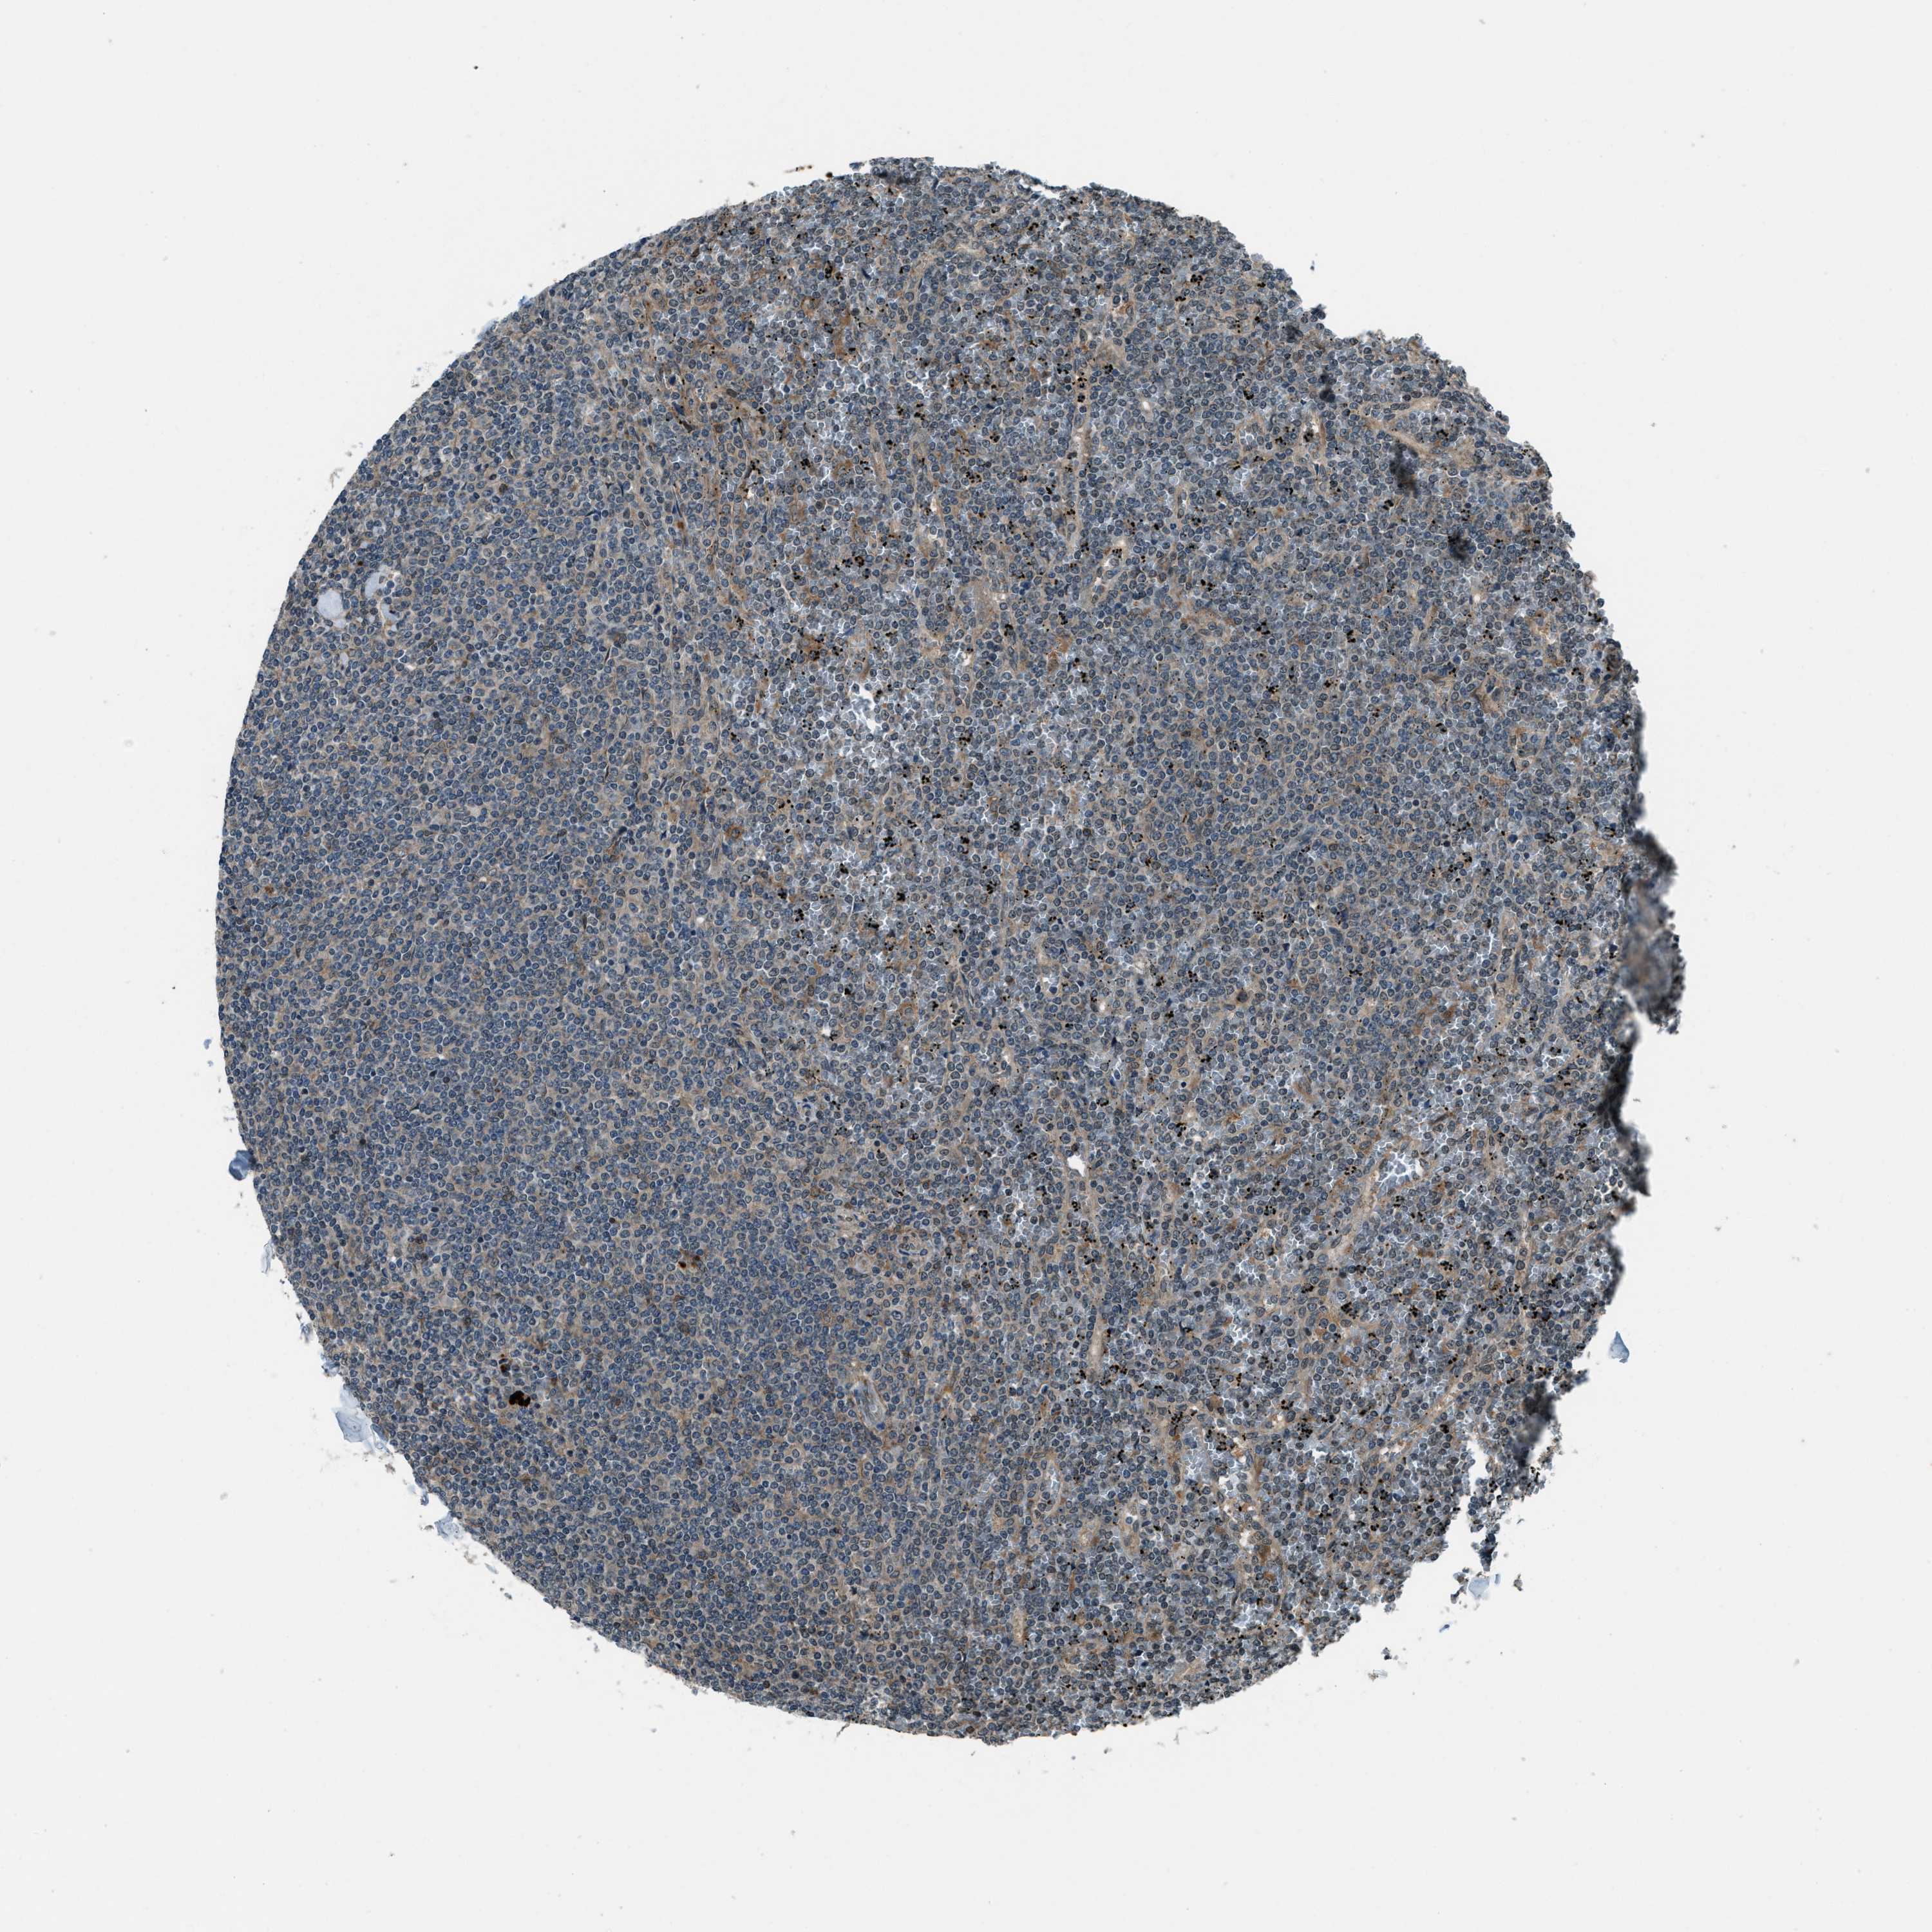

CANCER LYMPHOMA Show tissue menu

LYMPHOMA - Protein expressioni

A mouse-over function shows sample information and annotation data. Click on an image to view it in a full screen mode. Samples can be filtered based on level of antibody staining by selecting one or several of the following categories: high, medium, low and not detected. The assay and annotation is described here.

Each image is clickable and will lead to virtual microscopy that enables deeper exploration of all samples and also displays staining intensity scores, fraction scores and subcellular localization as well as patient and tissue information for each sample.

Antibody HPA020095

Antibody HPA020138

Antibody CAB010878

Antibody CAB080402

Staining

High

Medium

Low

Not detected

Intensity

Strong

Moderate

Weak

Negative

Quantity

>75%

75%-25%

<25%

None

Location

Nuclear

Cytoplasmic/membranous

Cytoplasmic/membranous,nuclear

Hodgkin's disease, NOS

Malignant lymphoma, non-Hodgkin's type, High grade

Malignant lymphoma, non-Hodgkin's type, Low grade